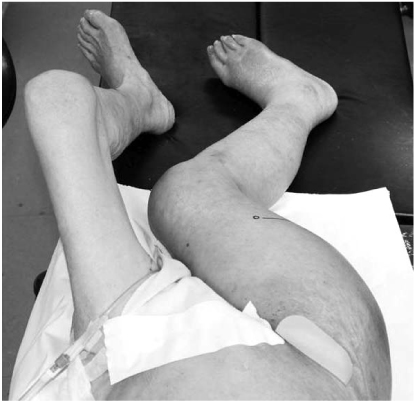

Fig. 1

(A, B) Preoperative radiographs; anteroposterior and translateral view showing subtrochanteric fracture with proximal migration of the femur shaft and deformed proximal fragment. Notice the anterior beak of the proximal fragment with severe angulation (arrow). Extensive calcifications are seen in the arteries.

Fig. 1 (A, B) Preoperative radiographs; anteroposterior and translateral view showing subtrochanteric fracture with proximal migration of the femur shaft and deformed proximal fragment. Notice the anterior beak of the proximal fragment with severe angulation (arrow). Extensive calcifications are seen in the arteries.